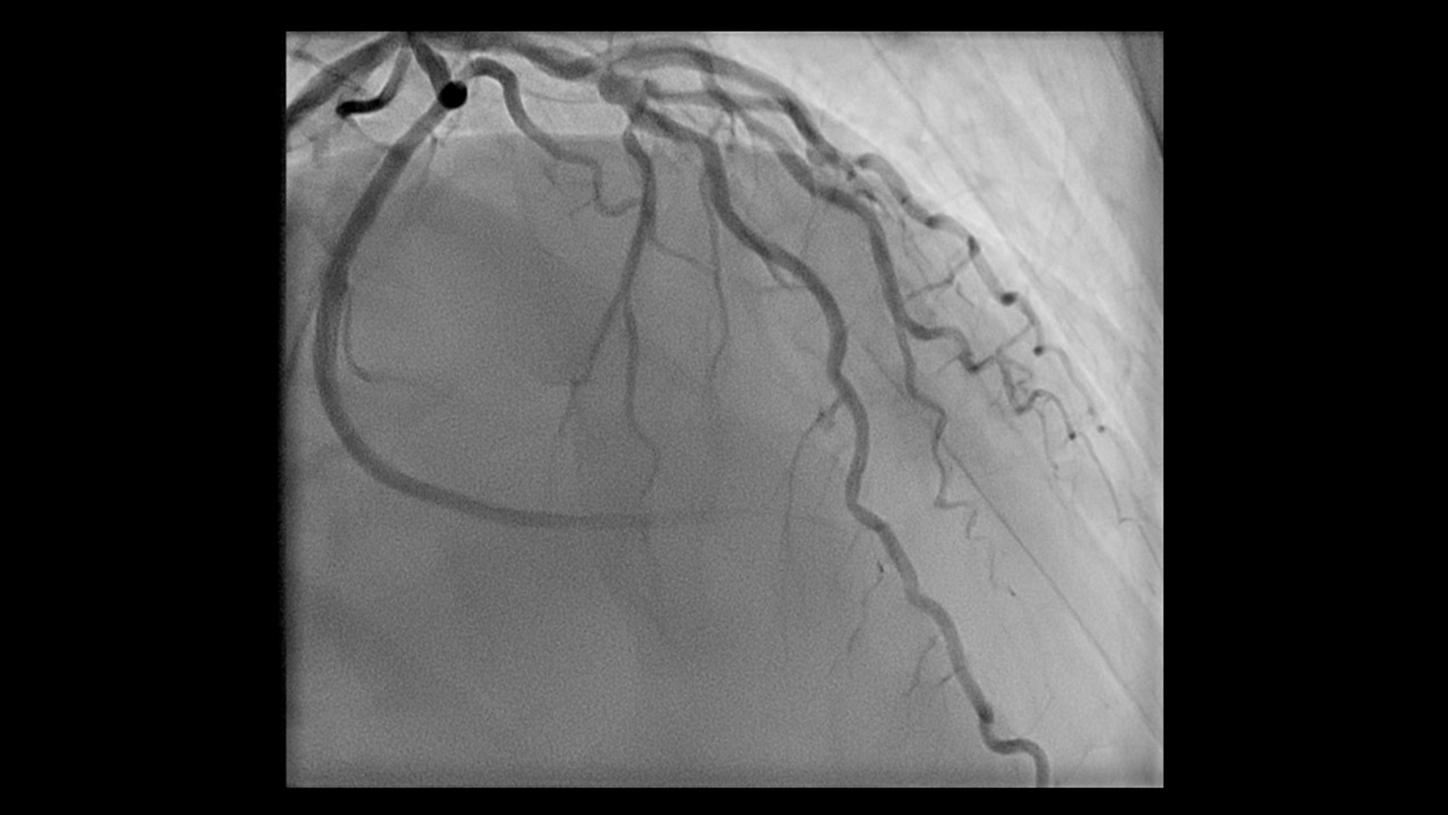

During minimally invasive procedures, it is critical to have a clear view of anatomies and devices. Yet complex imaging tasks or challenging patient conditions often impact image quality. OPTIQ AI delivers constant image quality1 defined by CNR in support of the ALARA principle, independent of patient or C-arm angulation. On top, an AI-powered algorithm reduces image noise in real time across different 2D imaging modes.

Make AI-powered imaging and clear insights your standard during interventions – with OPTIQ AI.